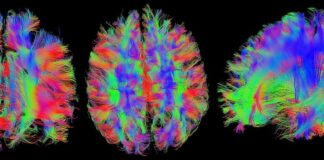

Descubren dos nuevas formas de plasticidad cerebral y el rol esencial...

Resultados importantes para el entendimiento del procesamiento de la información espacial y temporal en el cerebro

Una de las propiedades más interesantes del cerebro de...

Estudio utiliza herramientas de la ciencia de datos para detectar signos...

En esta investigación confluyen conocimientos obtenidos desde The Latin American Brain Health Institute (BrainLat), la Facultad de Ingeniería y Ciencias de la Universidad Adolfo...